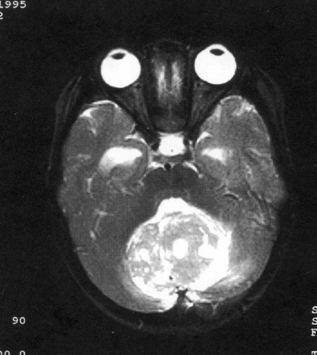

问题 病历摘要:??患儿男性,11岁。半年前开始出现行走不稳,常无故跌倒。半月前出现发作性剧烈头痛,伴恶心呕吐。体检:T36℃,P100次/分,R22次/分,BP100/60mmHg,神清,言语较缓慢,双眼外展约不及边,双眼侧视时有小幅度水平眼震。四肢肌力正常,右上肢肌张力较低,坐位姿势不稳,常不自主摇晃,双上肢指鼻不准,行走蹒跚步态,足距扩大,身前倾。 初步诊断考虑哪些疾病?提示:患儿行头颅?MR检查(见图)

选项 A.室管膜瘤 B.转移瘤 C.淋巴瘤 D.髓母细胞瘤 E.血管网状细胞瘤 F.星形细胞瘤 G.脉络丛乳头状瘤 H.多形胶质母细胞瘤

答案 ADFG